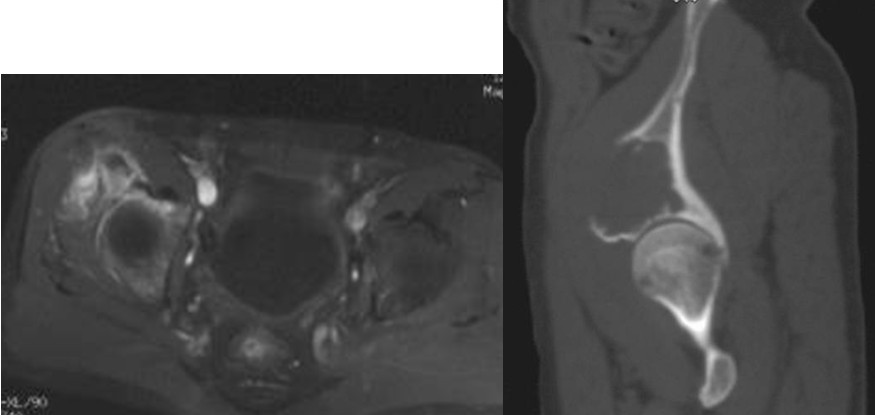

图4,女,52岁,乳腺癌髋臼转移, Harrington III型